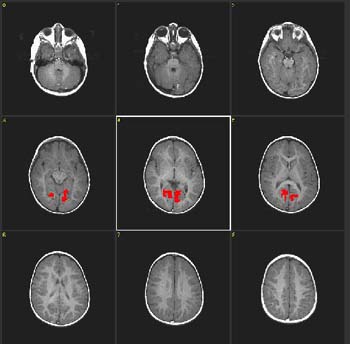

Case 3

| Patient | 4 year-old-boy with autism | ||||||

| Paradigm | ON: Presentation of flashing lights at 8 Hz, using special goggles OFF: Nothing. Patient sedated with nembutal | ||||||

| Statistics |

| ||||||

| Activation | Coronal cuts. The colored areas in the figure were obtained subtracting ON from OFF. Thus, the result shows "deactivation", which represent hyper extraction of oxygen occurring in the primary visual areas (V1). This finding is consistently found in young children either awake or under sedation. |